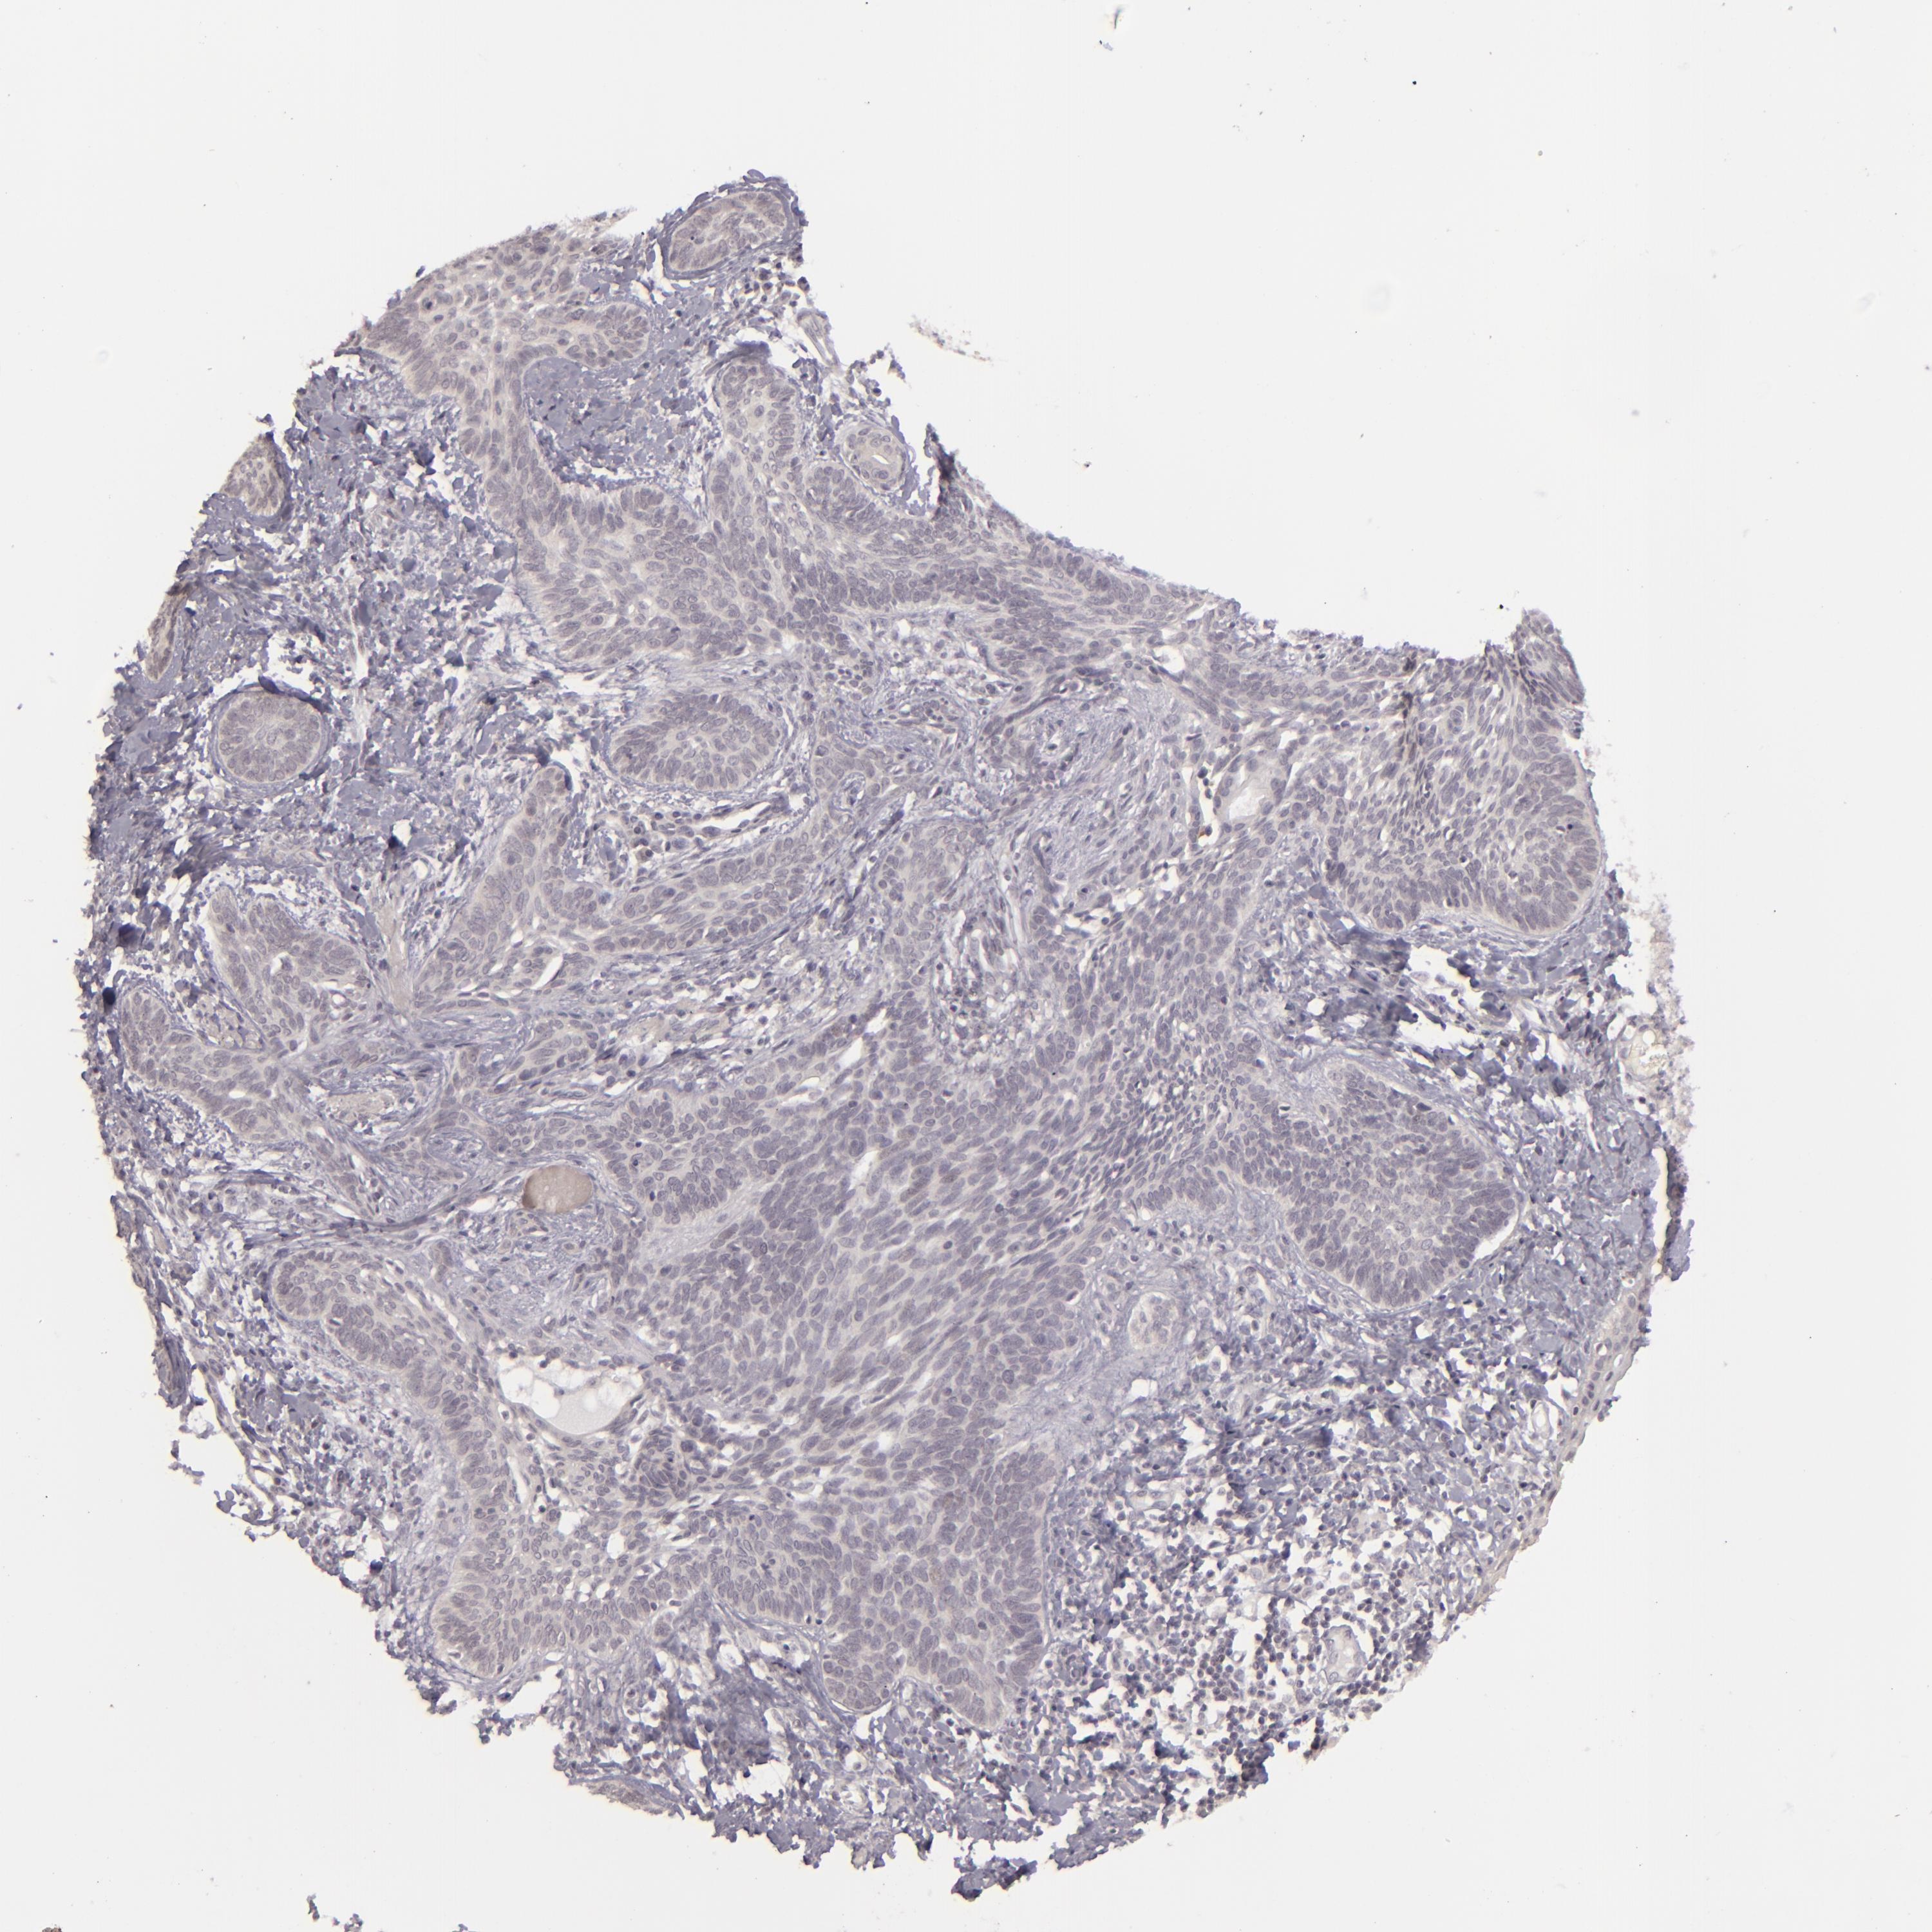

CANCER SKIN CANCER Show tissue menu

Basal cell and squamous cell cancer

SKIN CANCER - Protein expressioni

A mouse-over function shows sample information and annotation data. Click on an image to view it in a full screen mode. Samples can be filtered based on level of antibody staining by selecting one or several of the following categories: high, medium, low and not detected. The assay and annotation is described here.

Each image is clickable and will lead to virtual microscopy that enables deeper exploration of all samples and also displays staining intensity scores, fraction scores and subcellular localization as well as patient and tissue information for each sample.

Antibody HPA001733

Squamous cell carcinoma, NOS

Basal cell carcinoma